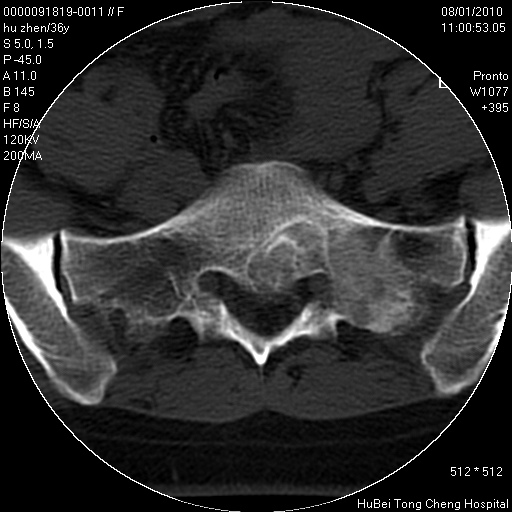

患者 女,36岁。右侧腰腿痛半月余。腰骶椎mr平扫偶然发现骶椎异常信号。

临床诊断:1)腰椎间盘突出症。2)骶椎肿瘤性病变?

骶椎ct平扫(层厚、层距均为5mm),图像如下:

考虑s1骨纤维异常增殖症。

良性骨病变,骨纤还是骨母细胞瘤?